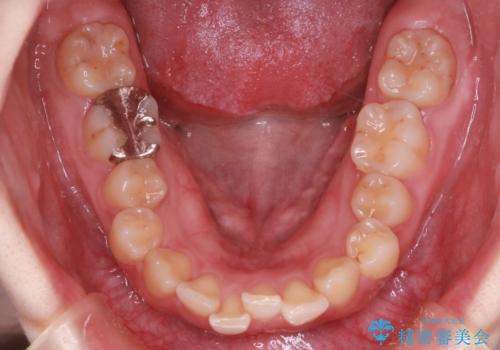

【インビザライン】前歯が出てるのを治したい

- 前歯の凸凹と前突を主訴に来院されました。

インビザラインにて治療をおこない、歯並びを改善することができました。